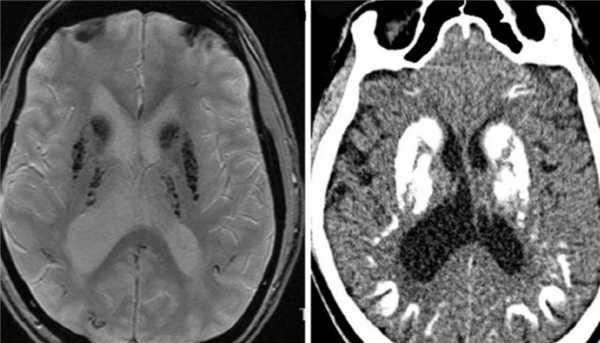

Болезнь Фара очень редкое наследственное заболевание, проявляющееся в кальцификации базальных ганглиев и зубчатого ядра. На Т2-зависимых МРТ ядра резко гипоинтенсивны, что соответствует кальцинатам, хорошо видимым на КТ. Нередко в области зрительных бугров обнаруживаются мелкие гиперинтенсивные очажки.

![болезнь Фара]()

МРТ и КТ головного мозга в аксиальной плоскости. Болезнь Фара.